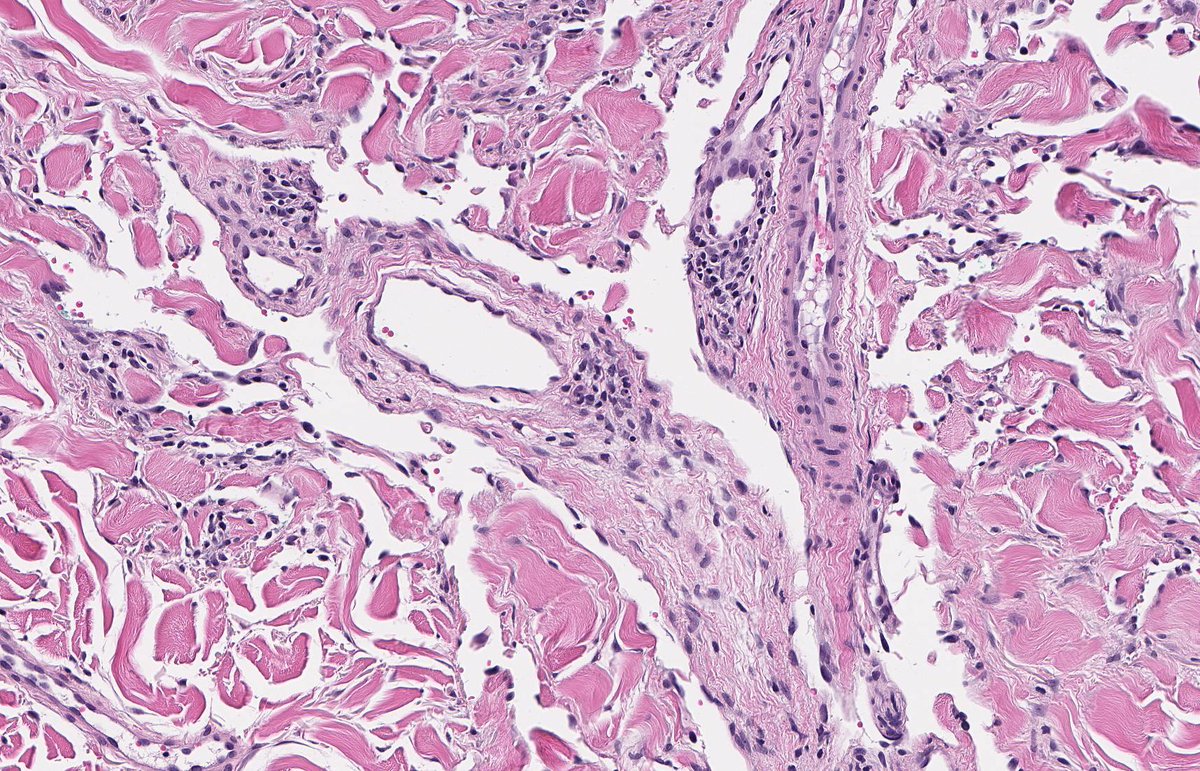

KAPOSI SARCOMA: IHC: HHV8. NB: ectatic, irregularly shaped, thin-walled vessels; collagen dissection; so-called 'promontory sign'; attenuated endothelial cells with eosinophilic cytoplasm; hyperchromatic nuclei showing mild atypia and inconspicuous mitotic activity.